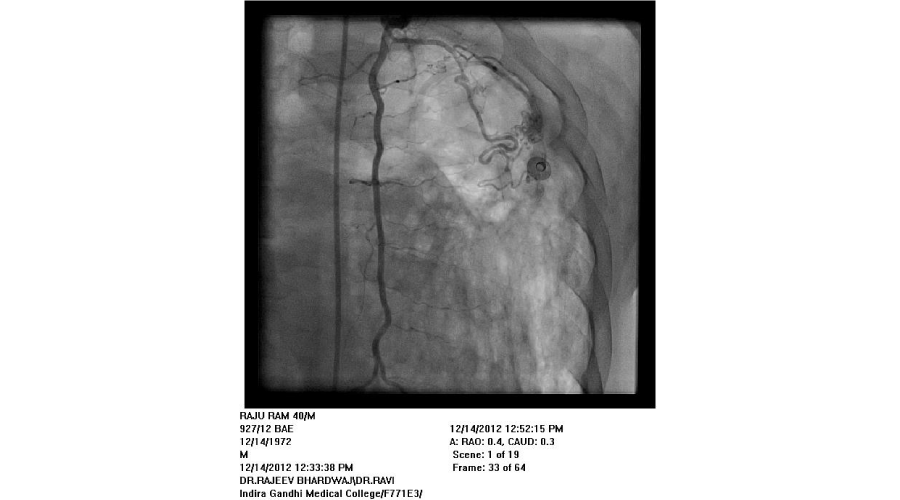

Patients admitted with moderate to severe hemoptysis in pulmonary medicine or general medicine department were the subjects of study. The patients were subjected to routine blood examination, X ray of chest, and CT scan of chest (Except in emergent situation). If required, bronchoscopy was done to localize the side of bleeding and for diagnostic purposes. Informed consent was taken from all patients. Commonest approach was from right femoral artery puncture. Seven French sheath was inserted in the femoral artery with the help of Seldienger technique. According to the protocol, bronchial arteries, intercostal arteries, subclavial arteries and its branches including the internal mammary arteries were selectively hooked with a catheter and contrast was injected into these arteries to see for the signs of bleeding. Initial attempt was made to see for bleeding source on the side suggested by X-ray or CT scan or bronchoscopy. Before the completion of procedure, vessels of other side were screened. If no bleeding vessel was found after screening on both sides, pulmonary arteriography was done with pig tail catheter to see for the source of bleeding from pulmonary artery. An artery was considered abnormal/ potential bleeder, if extravasation of contrast, aneurysm, increased caliber with tortuosity, vascular tufts, arterio-arterial or arterio-venous fistulas were seen. Once diseased artery was identified, it was selectively cannulated with a catheter. Most commonly used catheters were right Judikin, Cobra I, and Simmon I. The vessels were hooked deeply with the catheter, with the support of .018 inch guide wire. The vessel was then embolized with poly vinyl alcohol (PVA) particles mixed with contrast agent. The particles were injected till vessel was occluded or reflux of contrast was seen. If a vessel could not be hooked deeply, a micro-catheter was passed through the catheter and PVA particles were injected through micro-catheter. Size of particles used was 500-700 microns. If it was difficult to cannulate the branches of subclavian artery selectively, due to fibrosis, the artery was approached from radial artery puncture. Criteria used for successful embolization was that all diseased arteries were embolized. If spinal artery was seen on cannulation of a bronchial artery, the embolization was done distal to its origin to avoid inadvertent embolization of spinal artery.

We found that most of the cases required embolization of multiple vessels. In around half of the patients, both bronchial and systemic vessels required embolization. In around one fourth of patients, only bronchial and in another one fourth, only systemic vessels were the source of bleeding. In contrast to other studies, out of 192 vessels embolized, around 37% vessels were arising from subclavian arteries, (including 10% internal mammary arteries) and in 27% intercoastal arteries were the source of bleeding. Swansen et al., embolized the following arteries: right bronchial artery (34), left bronchial artery (11); combined right and left bronchial trunk (9); intercostal arteries (45); right internal mammary artery (8); left internal mammary artery (8); inferior phrenic artery (10); lateral thoracic arteries (3); thyrocervical trunk (2); and a left gastric artery (1) [11]. The complications of BAE in this study included subintimal dissection in two patients (4%), arterial perforation by a guide wire in one patient (2%), and reflux of embolic material into the aorta without adverse sequelae in one patient (2%). Pleuritic chest pain post procedure occurred in two patients (4%), shoulder pain post procedure in one patient (2%), and transient dysphagia in one patient (2%). One patient developed a groin hematoma at the puncture site.(Figures 1-5)